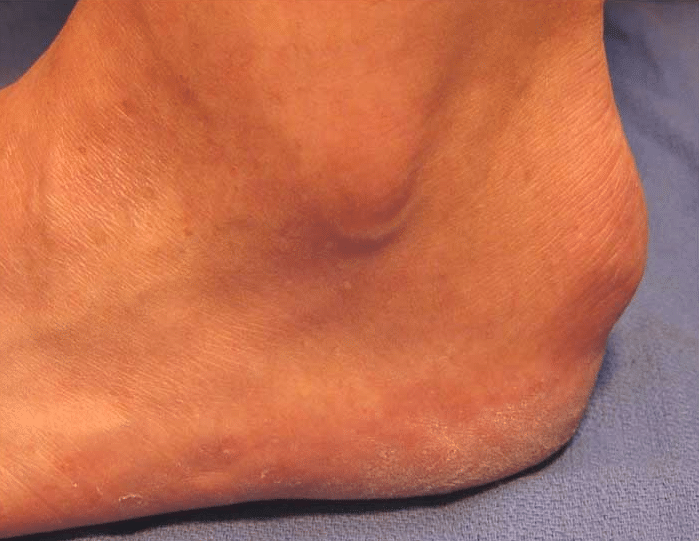

Inflammation of the Achilles’ tendon where it inserts into the calcaneus (heel bone) is known as insertional tendonitis. It is often associated with an abnormal bony prominence just deep to the tendon known as Haglund’s deformity or pump bump. This may play a role in rubbing on the deep aspect of the tendon to cause pain and inflammation in the tendon and surrounding soft tissues. If large enough, it can also rub on footwear or even prevent the wearing of certain shoes.

Haglund’s Deformity